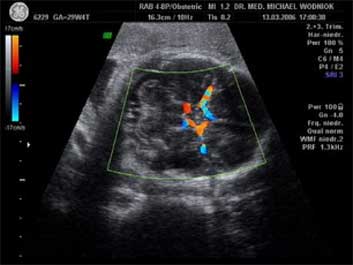

Voraussage der Entwicklung von schwangerschaftsverursachtem Bluthochdruck. Das Risiko für die Entwicklung dieser ernsten Schwangerschaftserkrankung liegt bei ungefähr fünf Prozent aller Schwangeren. Ergibt eine Doppleruntersuchung beider Gebärmutterarterien zwischen der 24. und 26. Schwangerschaftswoche (SSW) einen unauffälligen Befund, verringert sich das Risiko erheblich. Ist jedoch der Befund nicht in Ordnung, ist mit einer Wahrscheinlichkeit von etwa 35% für das Eintreten dieser Komplikation zu rechnen! Folglich wird die Betreuung der Schwangeren entsprechend intensiviert werden müssen und regelmäßige Doppler-Kontrollen werden durchgeführt.